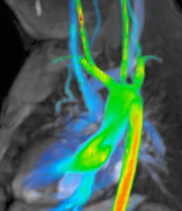

Description: Congenital heart diseases are heart problems that children are born with. These diseases range from simple to complex and many require surgery or other procedures.

Why MRI: Heart MRI is used to capture images in all types of congenital heart disease and at all ages. It can be used to help determine if and what type of surgery might be needed. It can also be used after surgery for routine follow up and check if there are any complications.

Heart MRI captures images of the heart and blood vessels to help see exactly the location and size of the structures. Sometimes 3D models are made to help see everything. Heart MRI can also measure flow in blood vessels and measure how well the heart muscle is pumping.

Images: ASD, 3D aorta, Flow in single ventricle